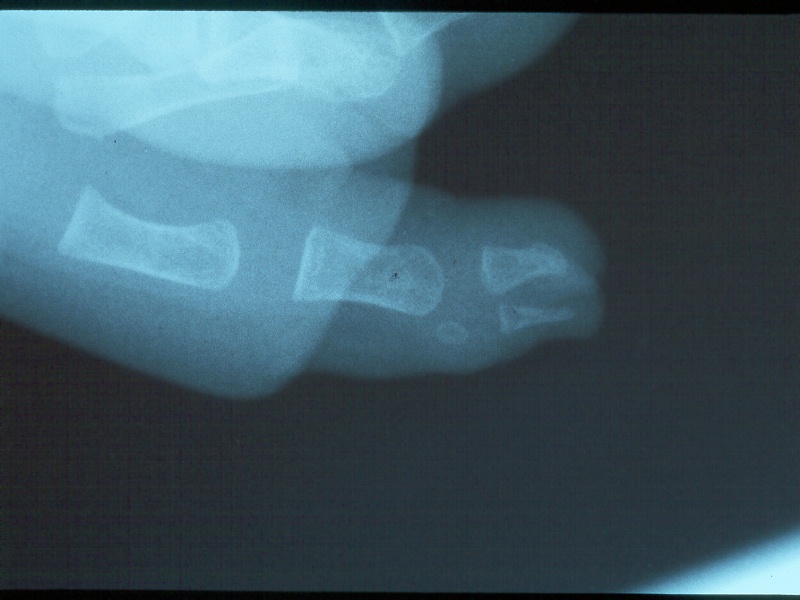

Clinical Example: Polydactyly

polydactyly